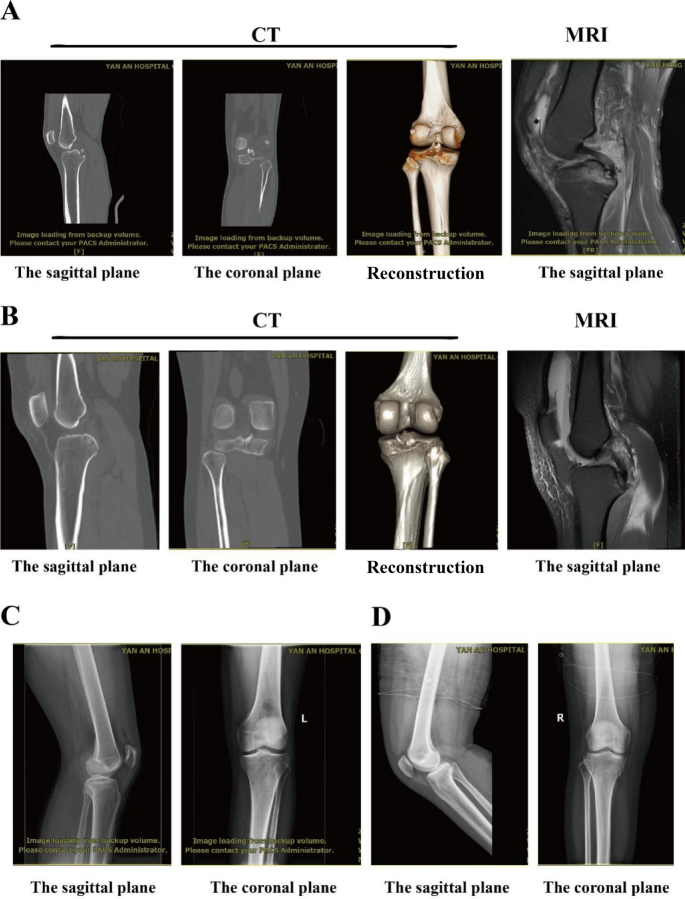

The same surgeon performed Open Reduction and Internal Fixation (ORIF) reconstruction procedures. The surgeries adhered to standard protocols, including anesthesia induction, establishing the conventional surgical position, routine sterilization, and applying an inflatable tourniquet for hemostasis. Given the fragmented nature of the fracture pieces, anatomical alignment was restored by securing them through the insertion of absorbable Bone Anchor Nails. All patients underwent surgery in the prone position, with spinal or general anesthesia administration. A thigh tourniquet was applied to the operated leg following a knee examination, and it was deflated for procedures lasting longer than 120 min, with an additional 10–15 min if deemed necessary. During the surgical procedures, distinct cases of posterior cruciate ligament (PCL) avulsion fractures of the tibia within the knee joint were encountered (Fig. 2A, B). These cases demonstrated a consistent pattern of PCL insert avulsion, characterized by fracture pieces displaced inward and upward by approximately 2 cm. An incision, approximately 8 cm in length, was made in the popliteal fossa, centered on the positioning point. This facilitated the exposure and protection of the popliteal artery, popliteal vein, and popliteal nerve. The joint capsule was then incised to unveil the insertion point of the tibial intercondylar spinous posterior cruciate ligament. In fracture displacement and avulsion, the distal end of the insertion point underwent expansion and tapping.

(A and C) Radiological images of Patient 1’s PCL avulsion fracture before and after the operation, respectively. (B and D) Radiological images of Patient 2’s PCL avulsion fracture before and after the operation, respectively.

One or two composite suture anchors (4.75 mm x 19.1 mm, ARTHREX) with threads were strategically inserted, and protective sutures were utilized to accurately knit and suture the posterior cruciate ligament (Fig. 3 AB, CD). The fractured end was anatomically reduced, and the tension of the cruciate ligament was strictly verified. The joint cavity underwent a thorough cleansing, being flushed with physiological saline. The joint capsule was precisely repaired, and the wound was sutured. Subsequently, a pressure bandage was applied, and the tourniquet was released. A post-operative follow-up X-ray was done to confirm the surgical accuracy (Fig. 2C, D). To further stabilize the lower limb, external fixation with a lower limb brace was initiated.